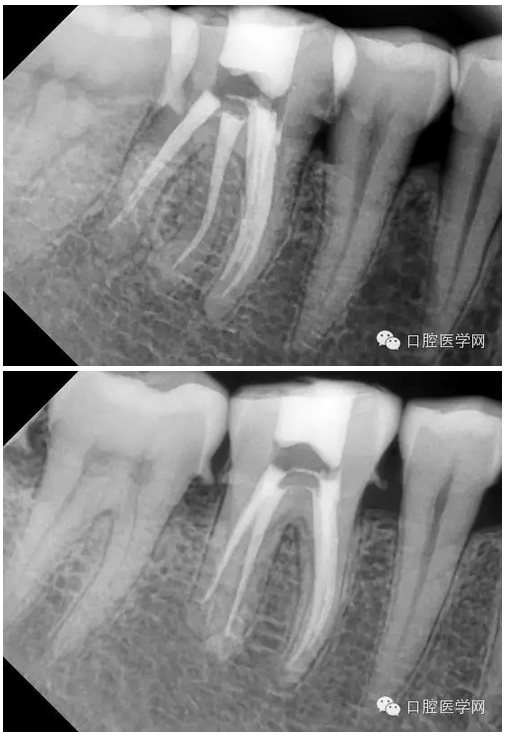

下六五根管治療一例

檢查:#46牙頰側(cè)小洞,探(++),叩(-),冷熱(+++),咬頜正常,牙齦未見不適,未見其它不適。

診斷:#46牙髓炎

治療計(jì)劃:#46根管治療+冠修復(fù)保護(hù)。